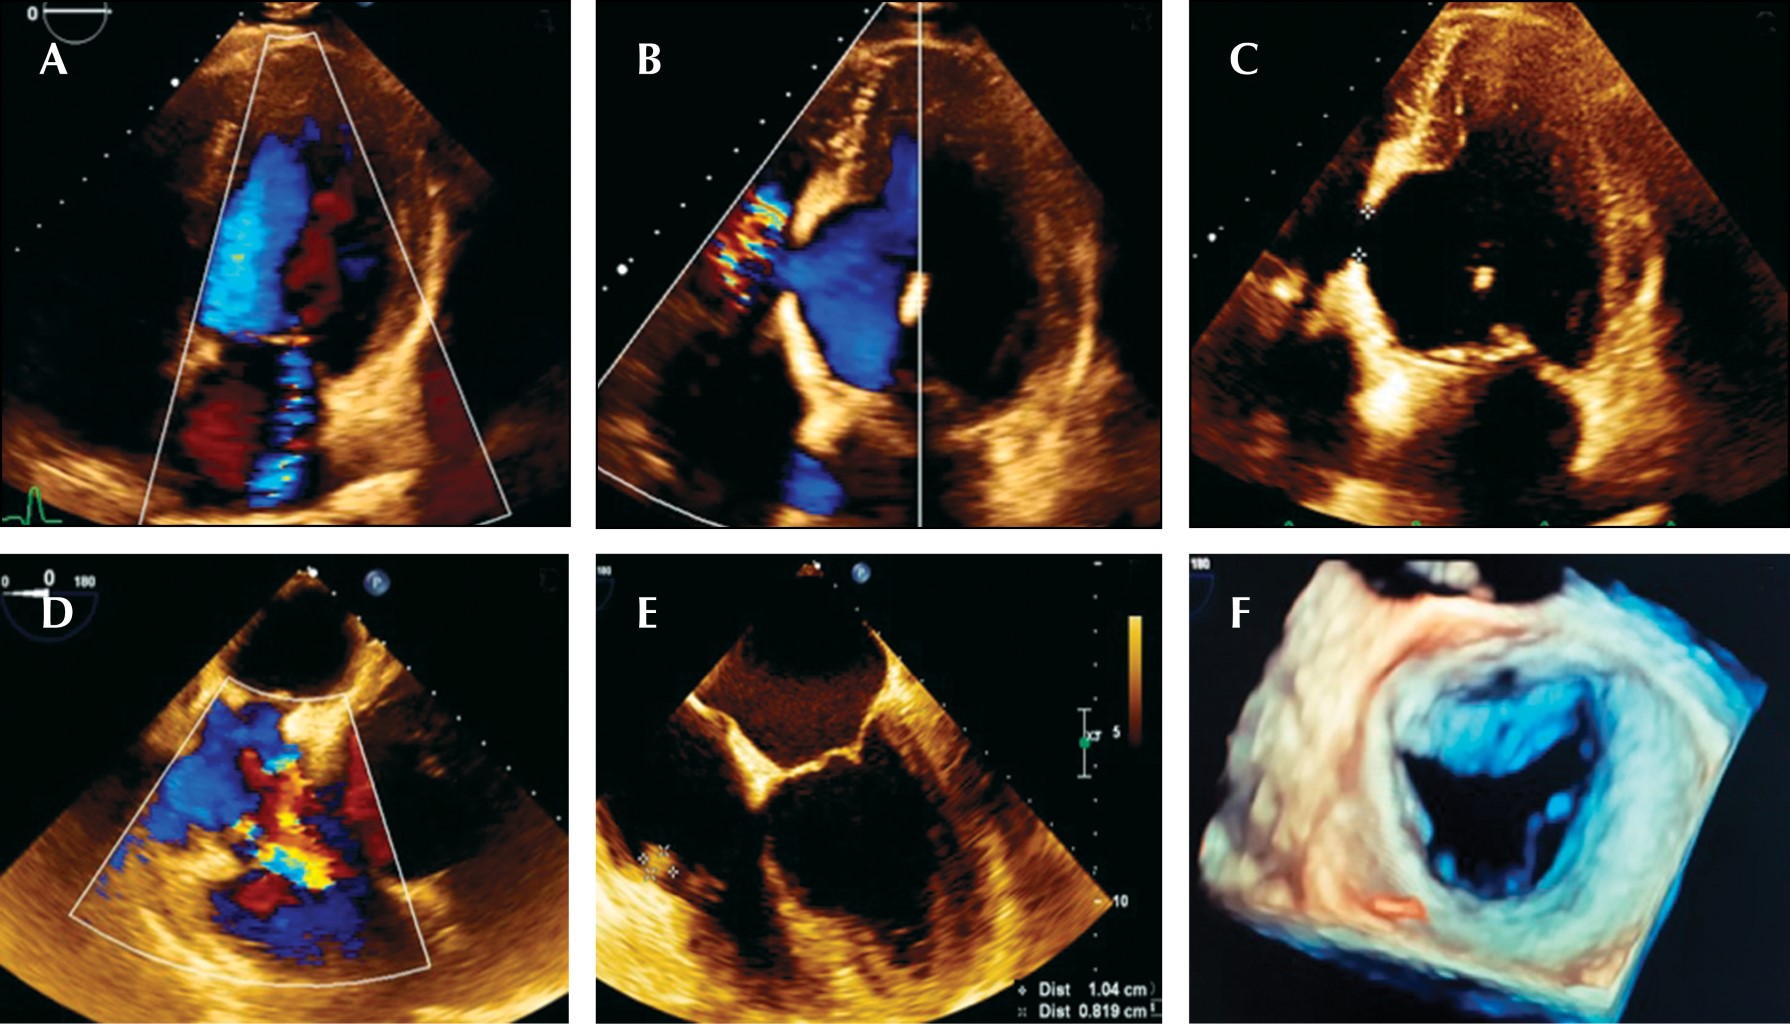

Endocarditis y espondilodiscitis como complicación de ruptura de aneurisma ventricular postinfarto

Aneurisma ventricular, infarto, endocarditis, espondilodiscitis.

El aneurisma ventricular postinfarto se define como una dilatación del ventrículo izquierdo o derecho en forma sacular que puede provocar su ruptura a nivel de la pared o septum ventricular y puede predisponer a endocarditis debido a la producción de turbulencias ocasionadas por cortocircuitos que ocasionan daño del tejido endocárdico con la consecuente colonización bacteriana y embolismos sistémicos. Una vez confirmado el diagnóstico, debe otorgarse tratamiento antibiótico y, en caso de complicaciones, valorarse el tratamiento quirúrgico. Se reporta el caso de un paciente masculino con antecedente previo de infarto agudo de miocardio, el cual acudió a urgencias por presentar datos de respuesta inflamatoria sistémica, evidenciándose endocarditis en válvula tricúspide y un aneurisma ventricular roto, condicionando fenómenos embólicos a columna dorsal, por lo que requirió tratamiento quirúrgico.

Figura 2